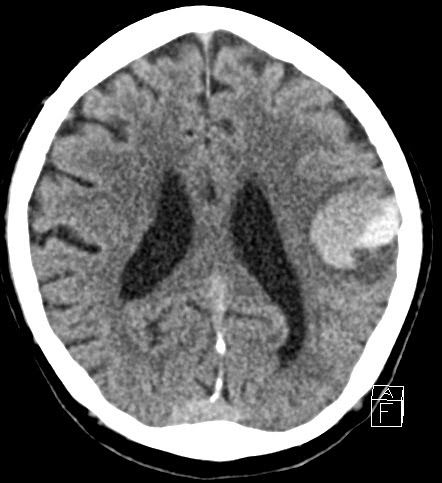

| hemorrhagic transformation on day-2 |